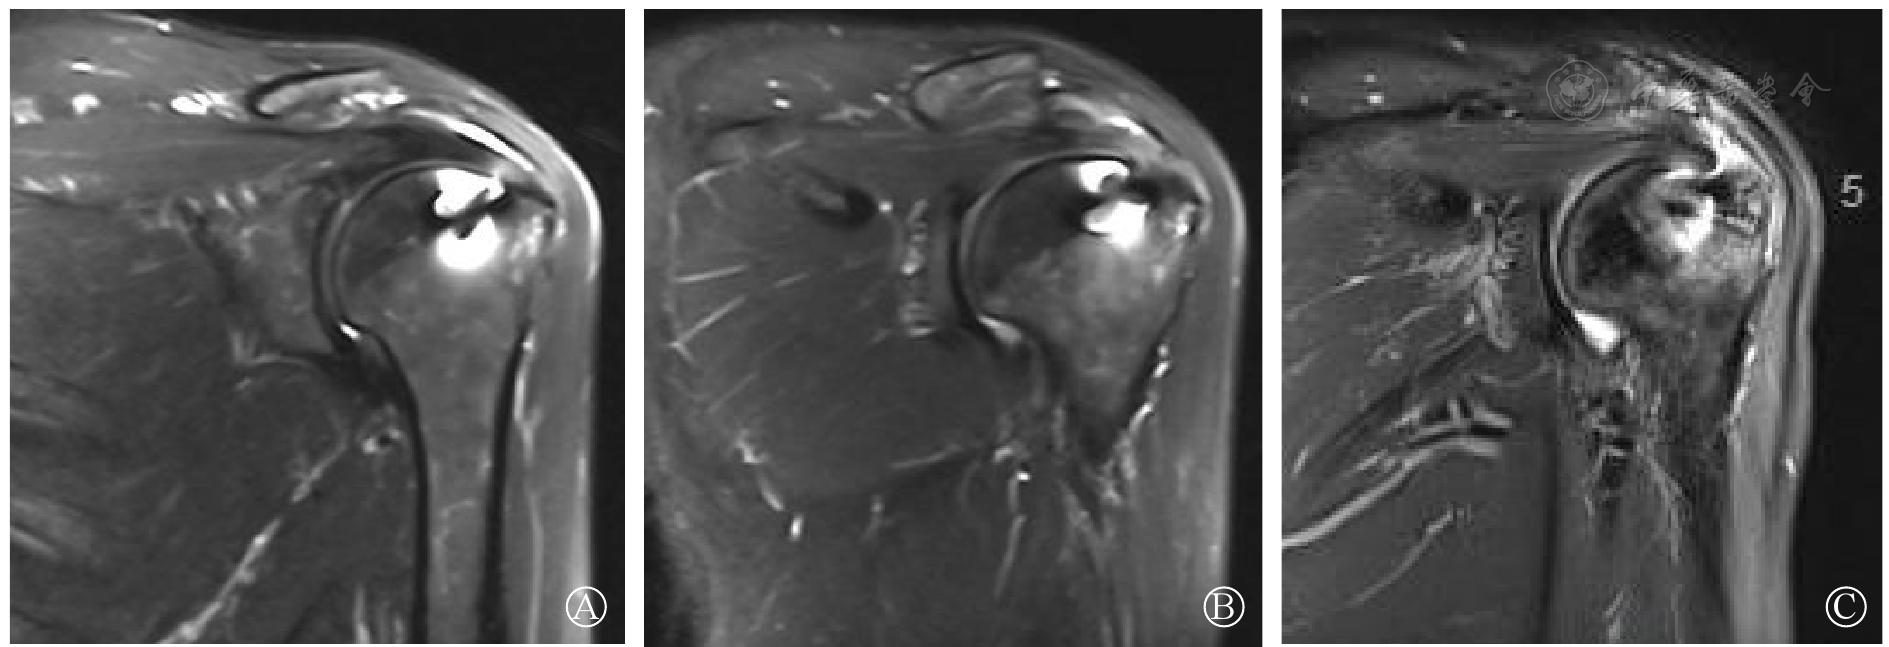

图2 患者女性,年龄51岁,左侧肩袖损伤,肩袖部分修补术后3个月(图A)、6个月(图B)、12个月(图C)MRI影像,Sugaya分型为Ⅳ,Ⅱ,Ⅱ

图3 患者女性,年龄58岁,右侧肩袖损伤,LHBT加强术后3个月(图A)、6个月(图B)、12个月(图C)MRI影像,Sugaya分型为Ⅳ,Ⅲ,Ⅱ注:LHBT为肱二头肌长头腱